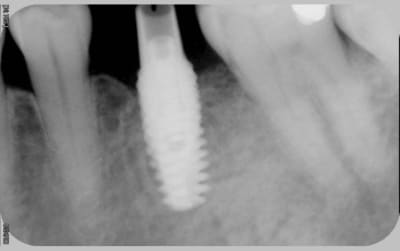

16/06/2010 à 16h05

comme promis

voici les cas vus ce mardi (il me manquait encore 10 patients: sur les 5 autres, tout est ok)

ps: la carie et le tartre sur la 7 ont été traités